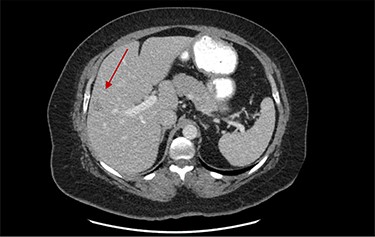

On assessment, the patient denied any symptoms related to her neuroendocrine tumor, including flushing, increased sweating, increased heart rate, wheezing, shortness of breath, diarrhea, weight loss or appetite changes. The only significant family history was a paternal and maternal grandfather with colon cancer. Imaging results were significant for computed tomography (CT) of chest demonstrating very small, but multiple, pulmonary nodules. A CT abdomen and pelvis demonstrated the known neuroendocrine tumor near the ileocecal valve (Fig. 1) as well as two poorly visualized liver lesions (Figs 2–4). The magnetic resonance imaging (MRI) demonstrated two separate one-centimeter lesions in segment 5 and 7 of the liver (Figs 5 and 6). The portal vein lacked normal left and right bifurcation; there was a circumferential right portal vein, which coursed anteriorly and superiorly and ultimately to the left lobe of the liver.

MRI image again demonstrating segment 5 metastatic lesion in close proximity to portal vein.